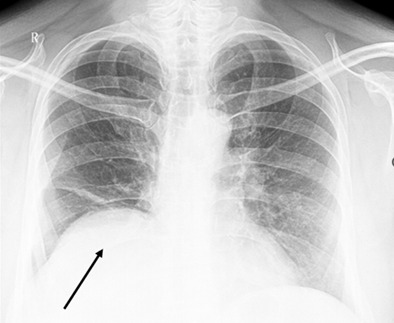

Рисунок 1. Обзорная рентгенограмма грудной клетки пациента Ж., тень кисты перикарда указана стрелкой

Представленный ниже клинический случай показывает пример бессимптомной кисты перикарда, диагностированный случайно, во время прохождения обзорной рентгенографии грудной клетки.

Пациент Ж., 50 лет, госпитализирован в плановом порядке в отделение хирургии КГП «Многопрофильной больницы №1» г. Караганды 29.10.2024 в плановом порядке с предварительным диагнозом «Округлое образование нижней доли правого лёгкого? Киста? Опухоль? Туберкулёз?». Больной не предъявлял каких-либо жалоб. Планировалось оперативное лечение в виде миниторакотомии с диагностической целью.

Наиболее распространенным рентгенологическим проявлением кист перикарда является четко очерченное, одно- или многоочаговое образование круглой или овальной формы с гладкими стенками и диаметром от 1 до 5 см. Однако диагностика кист перикарда может быть особенно сложной и из-за их редкости ещё больше усложняется. Кроме того, когда поражение обширное и затрагивает структуры средостения и грудной клетки, атипичная картина еще больше усложняет диагностику [4].

В нашем случае пациент не предъявлял каких-либо жалоб, ни со стороны дыхательной системы, ни со стороны сердечно-сосудистой системы. Подозрение на кисту возникло при прохождении рутинной обзорной рентгенографии грудной клетки, что послужило отправной точкой в истории его болезни. В дальнейшем использовался золотой стандарт диагностики кист перикарда – компьютерная томография грудной клетки. Однако, даже это не позволило поставить точный диагноз, в связи с чем было произведено оперативное вмешательство с диагностической целью. Выбор пал на миниторакотомию в связи с размерами образования: 19.5х10.5 см по данным КТ. Фактический же размер образования составил 20.0х14.0 см, а объём – один литр. Оперативное вмешательство выполнено без особых технических трудностей, время операции составило – 95 минут. Интраоперационно заключительный диагноз не вызывал сомнений, а гистологическое исследование препарата подтвердило его.

Таким образом, кисты перикарда – весьма редкая патология. Большинство пациентов бессимптомны, либо имеют разную симптоматику в зависимости от размера, локализации кисты и сопутствующих осложнений. Чаще всего это случайная находка у пациента без какой-либо симптоматики, обнаруженная при прохождении флюорографии/рентгенографии грудной клетки. Кисты перикарда могут быть выявлены при РГ ОГК, ЭхоКГ, РКТ и МРТ. При причинении дискомфорта пациенту, снижении качества его жизни, а также и с диагностической целью перикардиальные кисты подлежат хирургическому лечению.